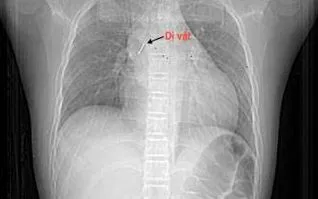

Trước đó, trẻ được khám tại bệnh viện tuyến dưới, xác định dị vật nằm sâu trong phế quản trung gian bên phải. Do dị vật sắc nhọn đâm xuyên thành phế quản, gây chảy máu và phù nề, nên việc gắp gặp nhiều khó khăn. Sau khi thủ thuật thất bại, bệnh nhi được chuyển khẩn cấp lên tuyến trung ương.